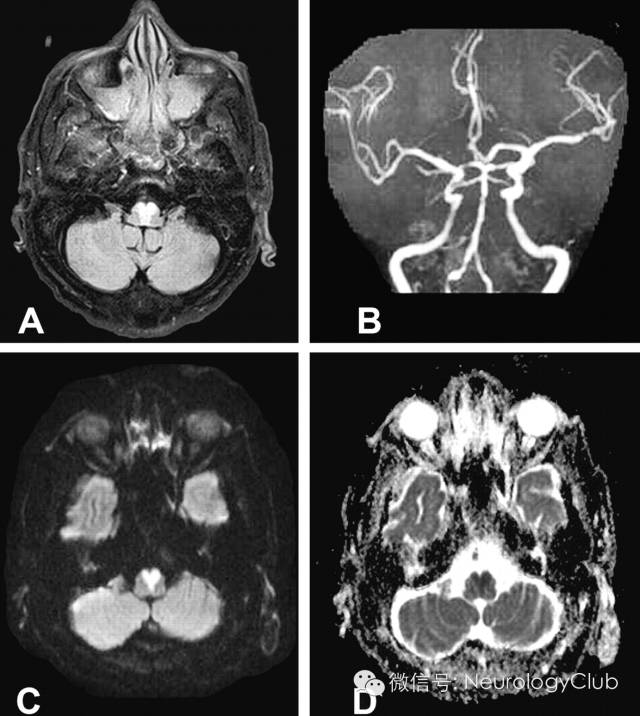

延髓内侧由椎动脉和脊髓前动脉分支供血,其中延髓内侧上1/3由椎动脉旁分支供应,下2/3由双侧脊髓前动脉及其汇合而成的前正中动脉延髓支供应。双侧延髓内侧梗死血管病理学改变以大动脉粥样硬化最为常见,其次是小穿支动脉病变,另外也有栓塞、动脉夹层、动脉炎或合并先天血管变异等病因报道。影像学特点头颅MRI检查,尤其是DWI对双侧延髓内侧梗死的早期诊断有很大的帮助。其影像学表现为磁共振显示双侧延髓内侧类似“心型”或“Y形”的长T1长T2信号影,DWI高信号,ADC低信号,符合梗死改变,具有特征性的诊断意义。

引自:The "heart appearance" sign in MRI in bilateral medial medullary infarction.Postgrad Med J. 2011 Feb;87(1024):156-7.

Anteromedial territory:前内侧区(血供大部分来自椎动脉)Anterolateral territory:前外侧区(血供大部分来自脊髓前动脉)ATT,ascending trigeminal tract(三叉神经上升支)DTT,descending trigeminal tract(三叉神经降支)HN,hypoglossal nucleus(舌下神经核)MLF,medial longitudinal fasciculus(内侧纵束)STT,spinothalamic tract(脊髓丘脑束)引自:The "heart appearance" sign in MRI in bilateral medial medullary infarction.Postgrad Med J. 2011 Feb;87(1024):156-7.